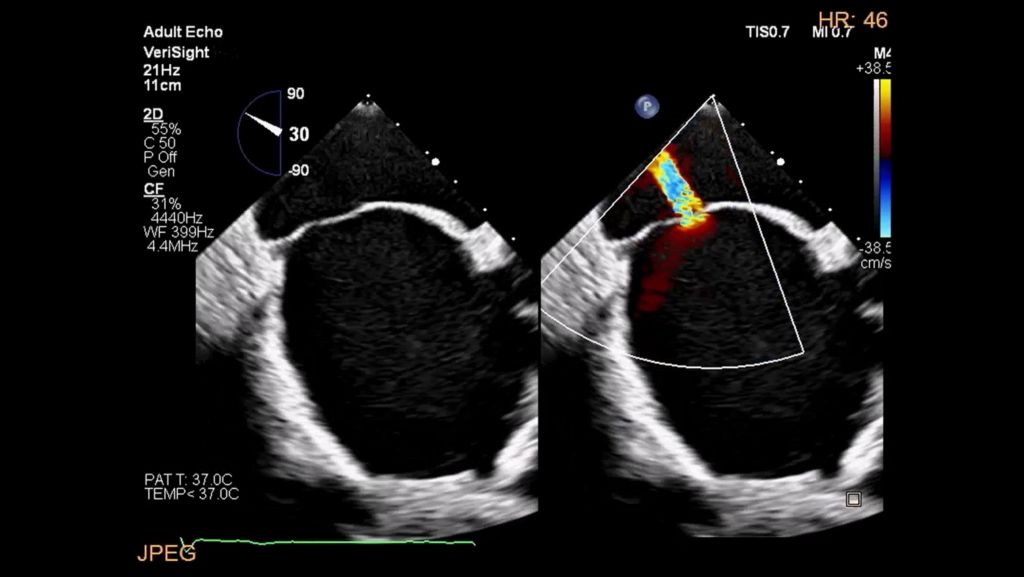

3. Sharkey et al. Advancing Precision in 3D Echocardiography: Incorporating 3D Markers to Aid Spatial Orientation. Journal of Cardiothoracis and vascular Anesthesia. Volume 38 Issue 9, September 2024, Pages 2070-2079. https://doi.org/10.1053/j.jvca.2024.05.009